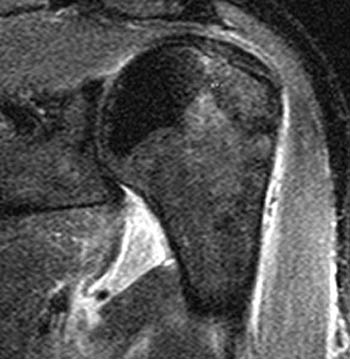

Glenohumeral ligament: анатомия и функции плечевого сустава